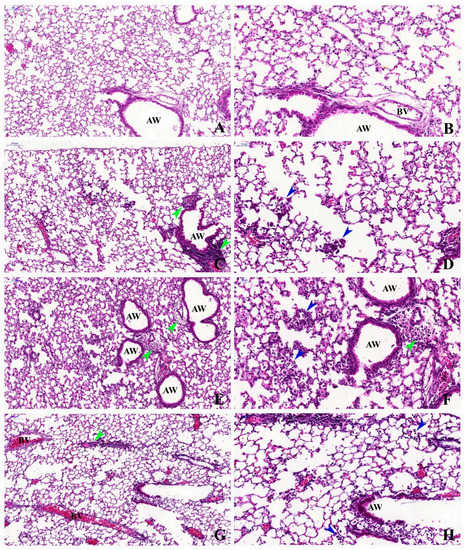

2.2. Histopathological Description